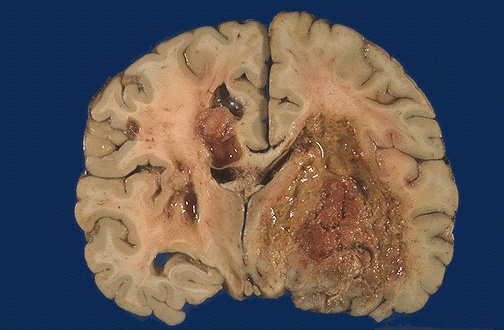

This is the worst possible form of glioma--a glioblastoma multiforme (GBM). These neoplasms are quite vascular with prominent areas of necrosis and hemorrhage. Note how this one has crossed the midline to the opposite hemisphere.